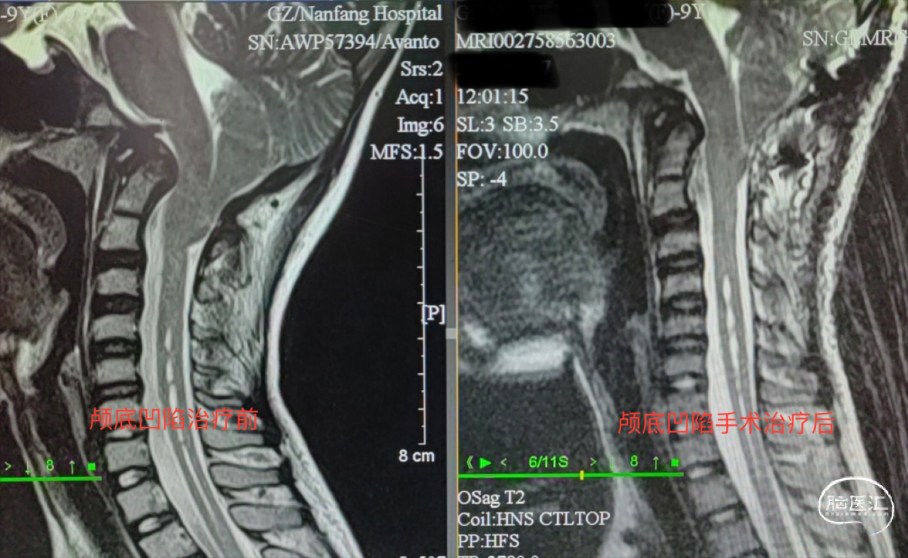

颅底凹陷症(basilarinvagination)的主要发病原因为先天性⻣质发育不良所致,由于在胚胎发⽣学上神经管在寰枕部闭合最晚所以先天性畸形容易发⽣在此区。少数可继发于其他疾病。本病分为2型:① 先天型:⼜称原发性颅底凹陷症,伴有寰枕融合、枕⻣变扁、枕⻣⼤孔变形、⻮状突向上移位甚⾄进 ⼊枕⻣⼤孔内,致使枕⻣⼤孔前后径缩⼩。在胚胎发育2~3周时由于胚胎分节的局部缺陷,寰椎不同程度地进⼊枕⻣⼤孔内有时与之融合等。近年来有⼈发现本病与遗传因素有关,即同⼀家族兄弟姐妹中可有数⼈发病。②继发型:⼜称获得型颅底凹陷症,较少⻅常继发于⻣炎、成⻣不全佝偻病⻣软化症、类⻛湿性关节炎或甲状旁腺功能亢进等导致颅底⻣质变软,变软的颅底⻣质受到颈椎压迫⽽内陷枕⼤孔升⾼,有时可达岩⻣尖,且变为漏⽃状。同时颈椎也套⼊颅底,为了适应寰椎后⼸,在枕⼤孔后⽅可能出现隐窝,⽽寰椎后⼸并不与枕⻣相融合。颅底凹陷症导致枕⻣⼤孔狭窄,后颅窝变⼩,压迫延髓、⼩脑及牵拉神经根产⽣⼀系列症状,合并有椎动脉受压出现供⾎不⾜表现。晚期常出现脑脊液循环障碍⽽导致梗阻性脑积⽔和颅内压增⾼。颅底凹陷常合并脑脊髓和其他软组织畸形,如⼩脑扁桃体疝、脊髓空洞症及蛛⽹膜粘连等。呼吸肌功能衰减常常使患者感觉⽓短,说话⽆⼒,严重者可能出现不同程度的中枢性呼吸抑制,睡眠性呼吸困难等。

南⽅医科⼤学附属南⽅医院神经外科脊髓与脊柱亚专业组在漆松涛主任及陆云涛教授的带领下先后针对不同类型颅底凹陷症300余例。总结积累了不同群体及不同类型颅底凹陷症的诊治经验,获得业界认同的同时也在国际级对应领域获得同⾏赞许。